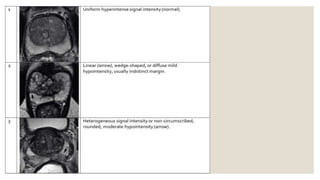

◦ Peripheral zone (PZ)

◦ 1: uniform high signal intensity (SI)

◦ 2: linear or wedge shaped hypointensity or diffuse mild hypointensity, usually indistinct margin

◦ 3: heterogeneous signal intensity or non-circumscribed, rounded, moderate hypointensity; includes others that

do not qualify as 2, 4, or 5

◦ 4: circumscribed, homogenous moderately hypointense focus or mass confined to prostate and <1.5 cm in the

greatest dimension

◦ 5: same as 4 but ≥1.5 cm in greatest dimension or definite extraprostatic extension/invasive behavior